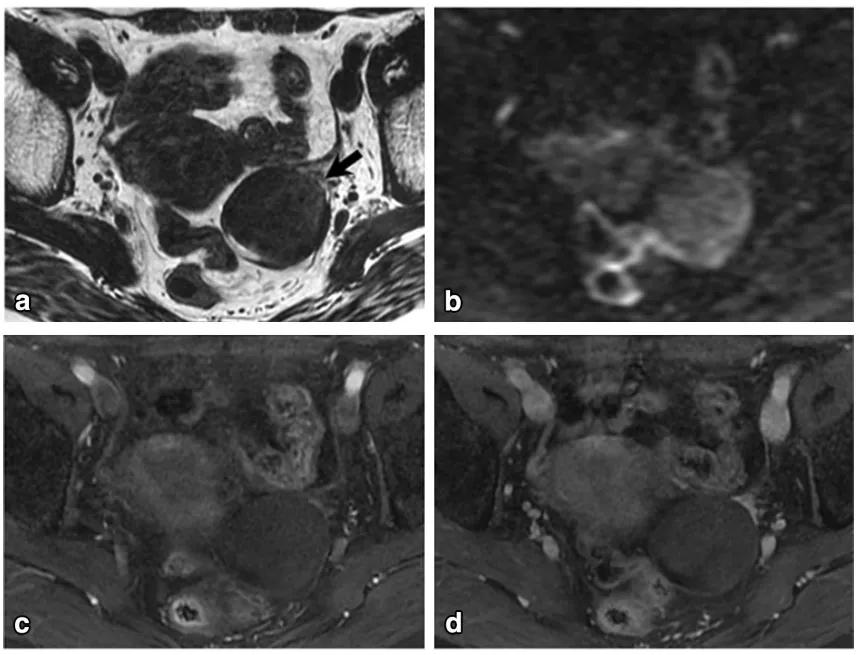

女,65 岁,左侧卵巢纤维瘤。图 a 箭头显示肿物 T2WI 呈低信号,DWI 未见明显扩散受限(b),增强扫描缓慢强化(c 增强早期,d 增强晚期)

女,70 岁,卵泡膜细胞瘤。图 a 增强扫描显示右侧卵巢肿物(白箭),同时子宫内膜增厚(图 a 白箭头及图 b 黑箭)。

女,32 岁,富于细胞性纤维瘤。右卵巢实性为主肿物,T2WI 稍高信号(图 a),DWI 高信号(图 b),增强扫描渐进行强化(c 增强早期,d 增强晚期)